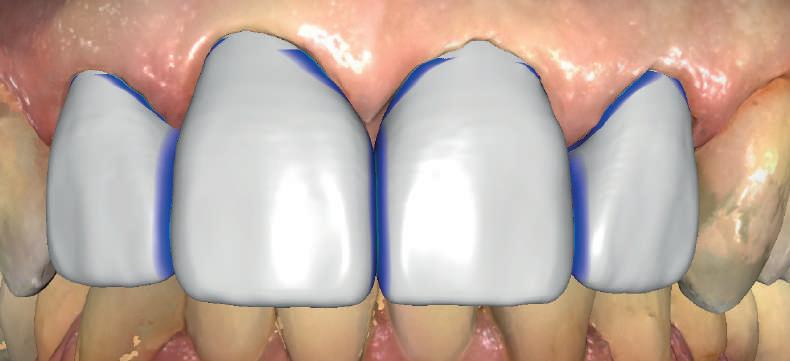

Atitudine: Până la dobândirea vindecării totale a ţesuturilor şi a implanturilor secundare s-au utilizat bonturi standard de titan. Fig. 18 prezintă bonturile individualizate maxilare şi mandibulare aplicate iar fig. 19 un prim-plan al cadranelor de partea dreaptă a pacientului, afişând finalizarea cazului la 15 luni după începerea tratamentului iniţial. Recesiile se pot obiectiva corespunzător 1.4. şi 1.3. În acest caz, s-a încercat minimizarea susceptibilităţii la recesie prin implicarea bonturilor temporare standard fixate cu şurub în cursul fazelor de vindecare pe toată durata etapelor iniţiale ale tratamentului.

În pofida acestor eforturi, totuşi, recesia a apărut în anumite regiuni unde implanturile erau plasate vestibular. Ulterior, s-a încercat grefarea ţesutui moale din jurul locaţiilor cu recesie, dar fără succes.

Rezultatul final al cazului 5 (fig. 19) prezintă recesie vestibulară de peste 2mm în jurul bonturilor cu sprijin implantar, fiind evidentă prezenţa unui ţesut moale foarte redus din cauza plasării vestibulare a implanturilor. Butler, Kinzer susţin premiza că trebuie să existe suficient volum osos vestibular, chiar şi atunci când implantul este plasat ideal, multe complicaţii fiind legate mai degrabă de poziţia implantului.

Cazul (5):

Bonturi conice utilizate ca bonturi temporare

Figurile

16, 17. Implanturile din prima etapă încărcate cu bonturi conice şi, în unele cazuri, omologii angulaţi.

18. Bonturile individualizate inserate.

19. Rezultat final la 15 luni după începerea tratamentului iniţial.

şi va induce resorbţie osoasă şi migraţia apicală a ţesutului (Saadoun & Touati). Dacă implantul nu este plasat mai palatinal şi la 3-4mm apical de marginea gingivală liberă pentru a asigura profilul de emergenţă adecvat, rezultatul estetic este compromis (Chu et al). Un studiu de 2 ani a demonstrat că implanturile poziţionate anterior au demonstrat o recesie uşor mai accentuată, decât implanturile posterioare (Bengazi et al). Plasarea vestibulară a implanturilor se poate vizualiza clar în cazul 5 (fig. 17) cu bonturile de vindecare în poziţie.

Proximitatea implanturilor adiacente

Se recomandă existenţa a cel puţin 3mm de os între două implanturi adiacente (Tarnow et al). În acelaşi caz 5, corespunzător 2.5. şi 2.6. distanţa la nivel inter-implantar este sub 2mm iar între bonturi sub 1mm (fig. 17). Întrucât ţesuturile inter-implantare nu au acelaşi nivel de suport ca în cazul dinţilor naturali, distanţa interdentară devine esenţială în anticiparea poziţiilor finale ale ţesutului moale.